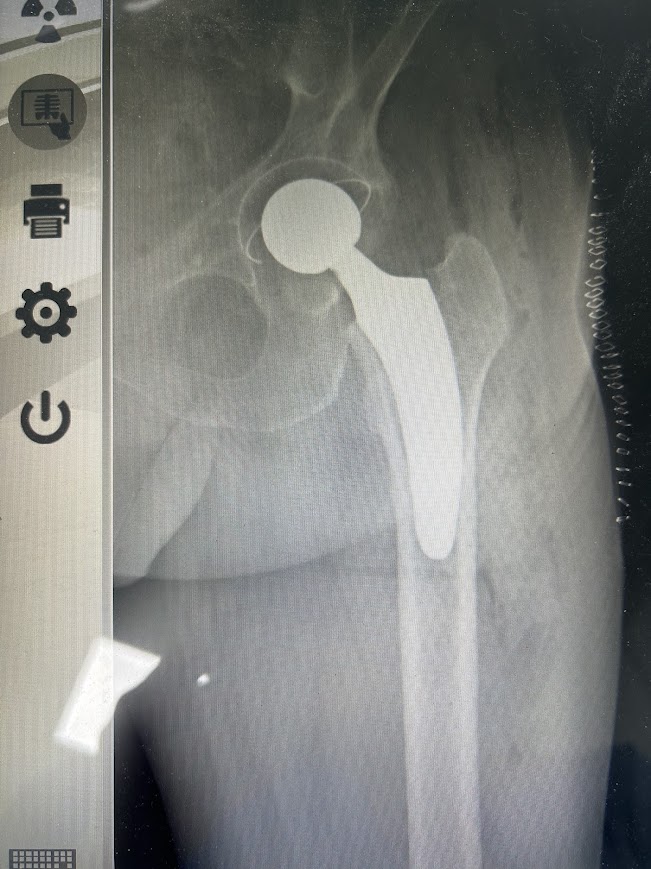

Η αρθροπλαστική ισχίου επιτυγχάνει την αντικατάσταση του κατεστραμμένου χόνδρου της άρθρωσης και του καταπονημένου οστού με ειδικά σχεδιασμένα εμφυτεύματα από μεταλλικά, πλαστικά ή κεραμικά υλικά. Αυτό επιτυγχάνεται μέσω μιας προσεκτικά σχεδιασμένης επεμβατικής διαδικασίας που επιδιώκει τη βέλτιστη ανακατασκευή της άρθρωσης και την επαναφορά της λειτουργικότητας.

Η επέμβαση διαρκεί 1 ½ – 2 ώρες. Ανάλογα με την περίπτωση η αναισθησία μπορεί να είναι επισκληρίδιος, ραχιαία ή ολική. Κατά τη διάρκεια της αρθροπλαστικής ο ιατρός, αφαιρεί την κεφαλή του μηριαίου και την αντικαθιστά με την τεχνητή άρθρωση.

Η τεχνητή άρθρωση αποτελείται από τον μηριαίο στειλεό με κεφαλή και την υποδοχή της κεφαλής (κυπέλλιο κοτύλης). Ο στειλεός και η υποδοχή της κεφαλής είναι κατασκευασμένα από τιτάνιο ενώ η κεφαλή του στειλεού είναι από μέταλλο ή κεραμικό υλικό.

Η ποιότητα των υλικών εξασφαλίζει τέλεια ενσωμάτωση. Το κυπέλλιο είναι επενδεδυμένο εσωτερικά με κεραμικό ή πολυαιθυλένιο (πλαστικό), το οποίο προσδίδει μακρά βιωσιμότητα ακόμη και στις περιπτώσεις που υπάρχει έντονη σωματική δραστηριότητα και πίεση.